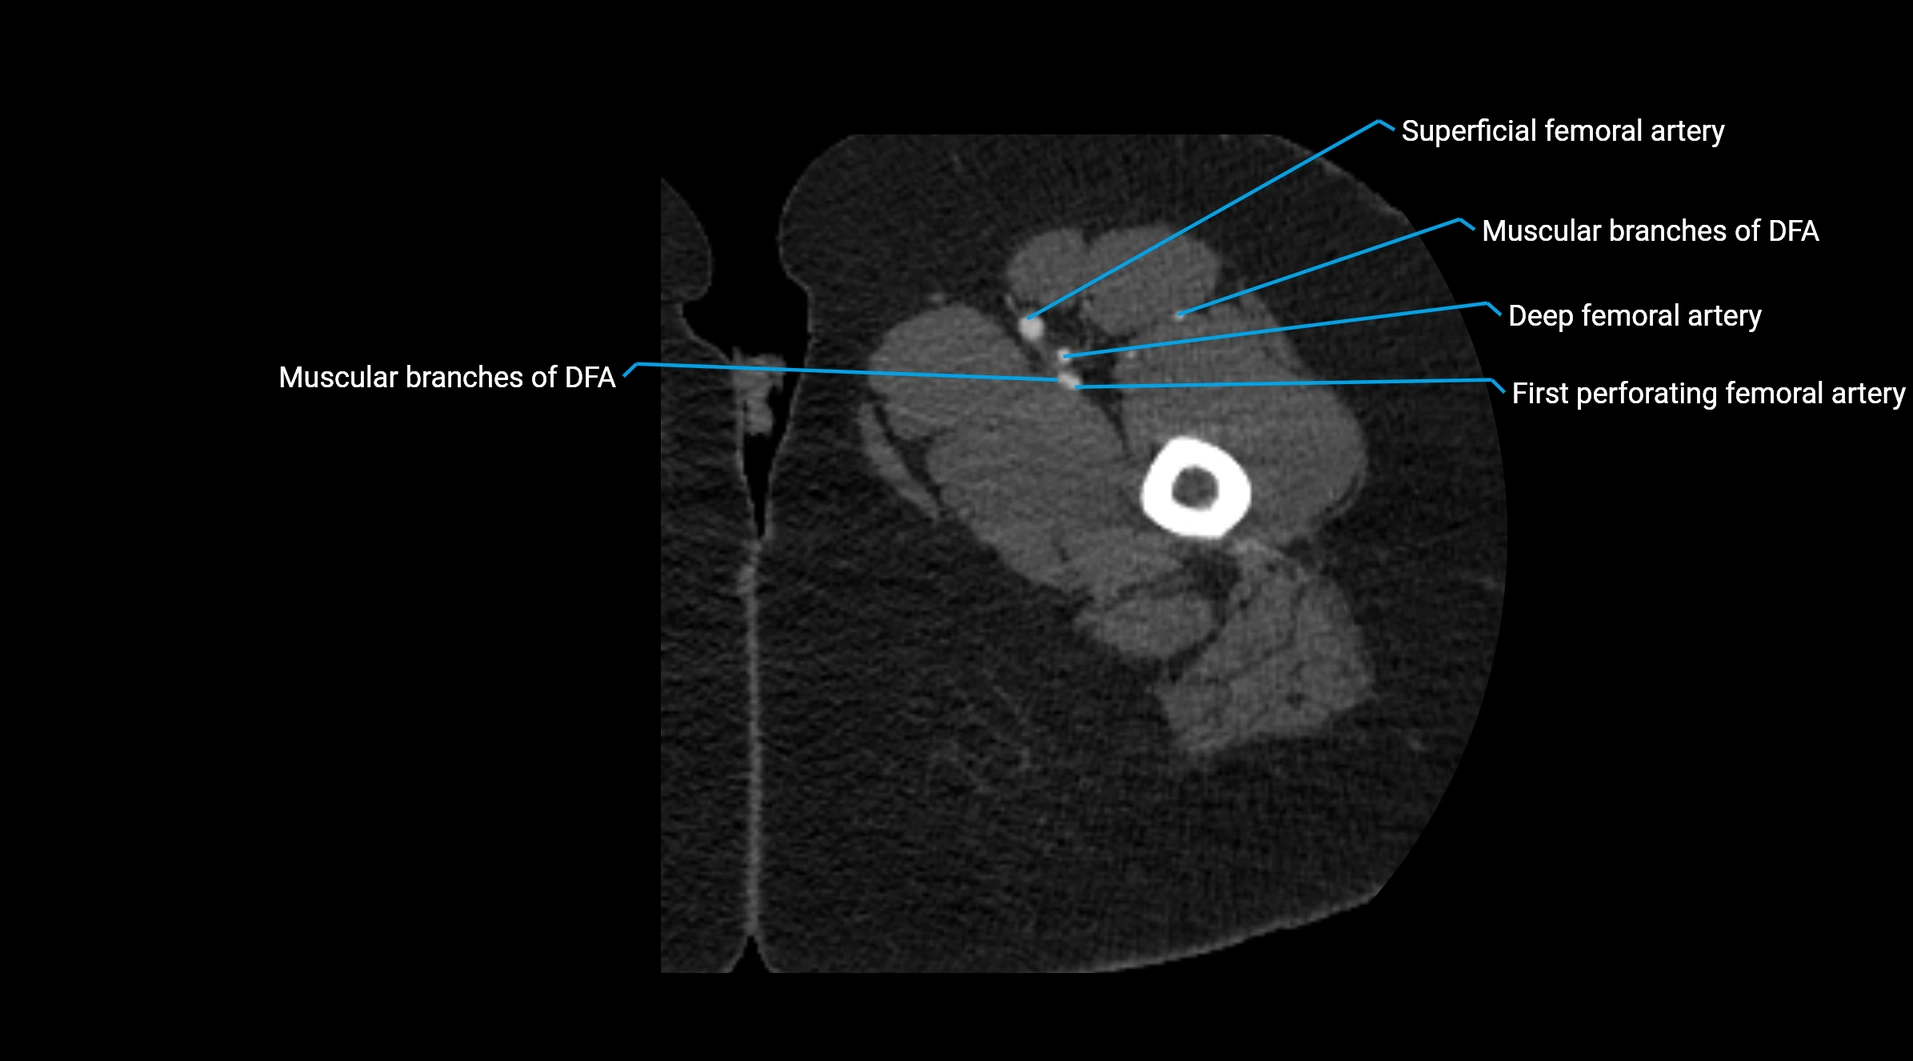

CT images

image